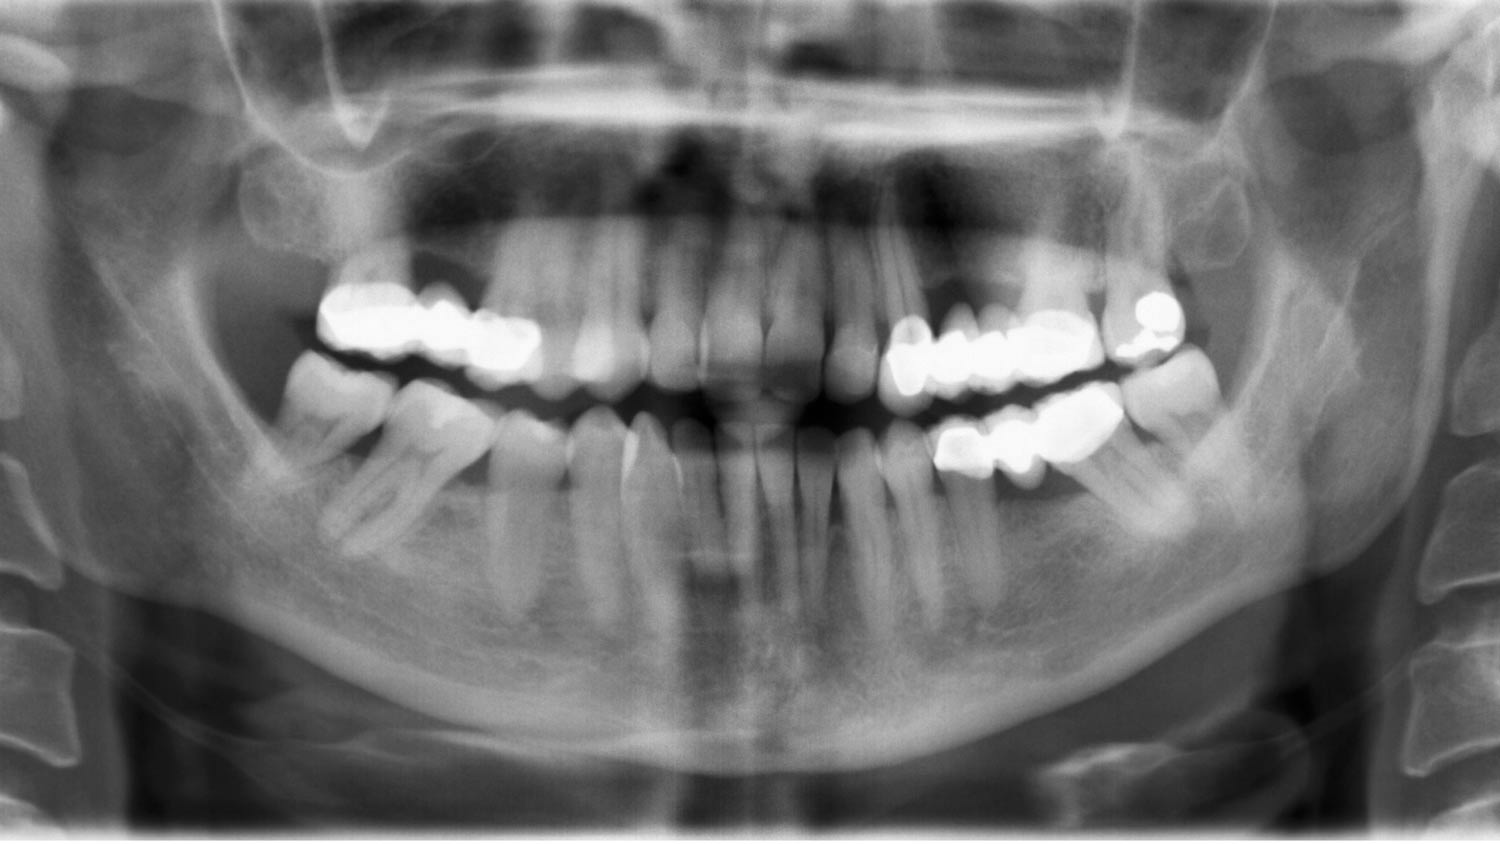

Lo primero era evaluar su estado dental y establecer un pronóstico a largo plazo. Para ello, se realizaron radiografías, registros fotográficos, impresiones y arco facial.

Esta paciente quería cambiar sus viejas prótesis de metal-cerámica, con más de 25 años, por algo más estético. Presentaba recesiones, zonas de atrofia, problemas en la arcada dental y estéticamente, una excesiva exposición gingival, márgenes irregulares y diferencias de color entre la restauraciones y sus dientes originales.

Había que intervenir de manera conjunta. Necesitábamos al doctor Rafael PLA García para cambiar las prótesis, al doctor Rafael PLA Martinez en implantaología y periodoncia, la doctora Julia Martinez en ortodoncia y a la doctora Marta PLA, para las restauraciones estéticas.